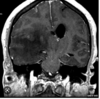

Which of the following mechanism of TBI is depicted in the CT?

1- Skull fracture

2- Contusion (bruise)

3- hematomas (blood clots)

4- lacerations (tear)

5- Diffuse axonal injury (nerve damage)

A